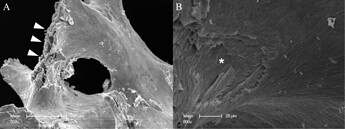

Fig. 1.

Overview about the microscopic structure and architecture of A the surface and B the side of an allogeneic cortical bone plate by scanning electron microscopy (SEM) at 100-fold magnification. SEM demonstrating the compact structure of allogeneic cortical bone plate that is suitable for a sufficient barrier and stabilization function